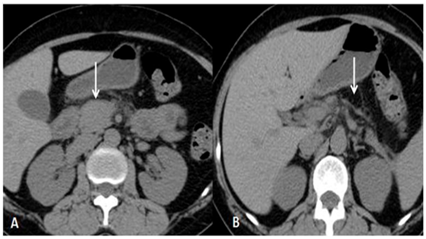

Computed tomography (CT) scan of abdomen showed oedematous pancreatic head (Figure 1A), with absence of pancreatic body and tail (Figure 1B). MRCP was done which showed pancreatic duct only in the head region with its non visualisation in the body and tail (Figure 2). These features were suggestive of dorsal pancreatic agenesis.

Figure 1 CT scan abdomen image showing oedematous pancreatic head (Figure 1A), with absence of pancreatic body and tail (Figure1B).